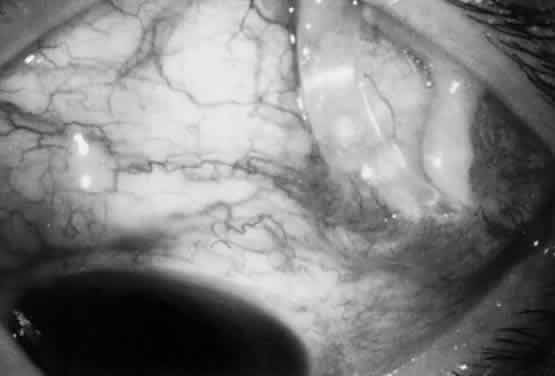

The filtration site is placed posteriorly near the equator in the latest generation of shunts. The morphologic features of these blebs are different from those of functional blebs at the limbus, as seen with a trabeculectomy. They are typically thick-walled, with prominent conjunctival vascularity, and are elevated over the reservoir (Fig. 1). Although the silicone tube and PMMA plates of the Molteno shunt are biologically inert and do not produce tissue necrosis, a thick fibrous capsule envelops the reservoir and tube (Fig. 2)25–29

Fig. 2. Histologic features of bleb surrounding a Molteno reservoir.